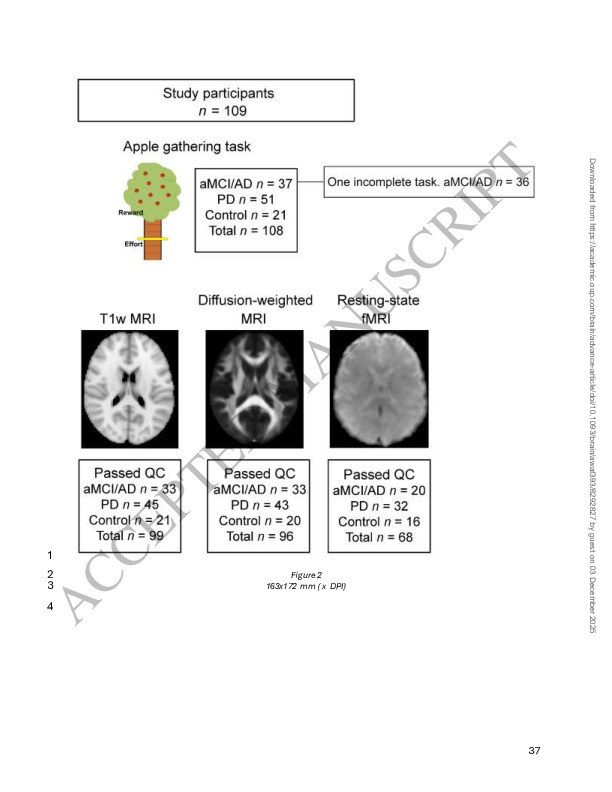

(2025). A transdiagnostic, multi-modal approach to understanding apathy: Methodological and analytical framework. NeuroImage: Reports, 5(4), 100289. 10.1016/j.ynirp.2025.100289

(2025). Apathy, effort-based decisions and brain integrity in Alzheimer’s and Parkinson’s diseases. Brain, p.awaf393.. 10.1093/brain/awaf393